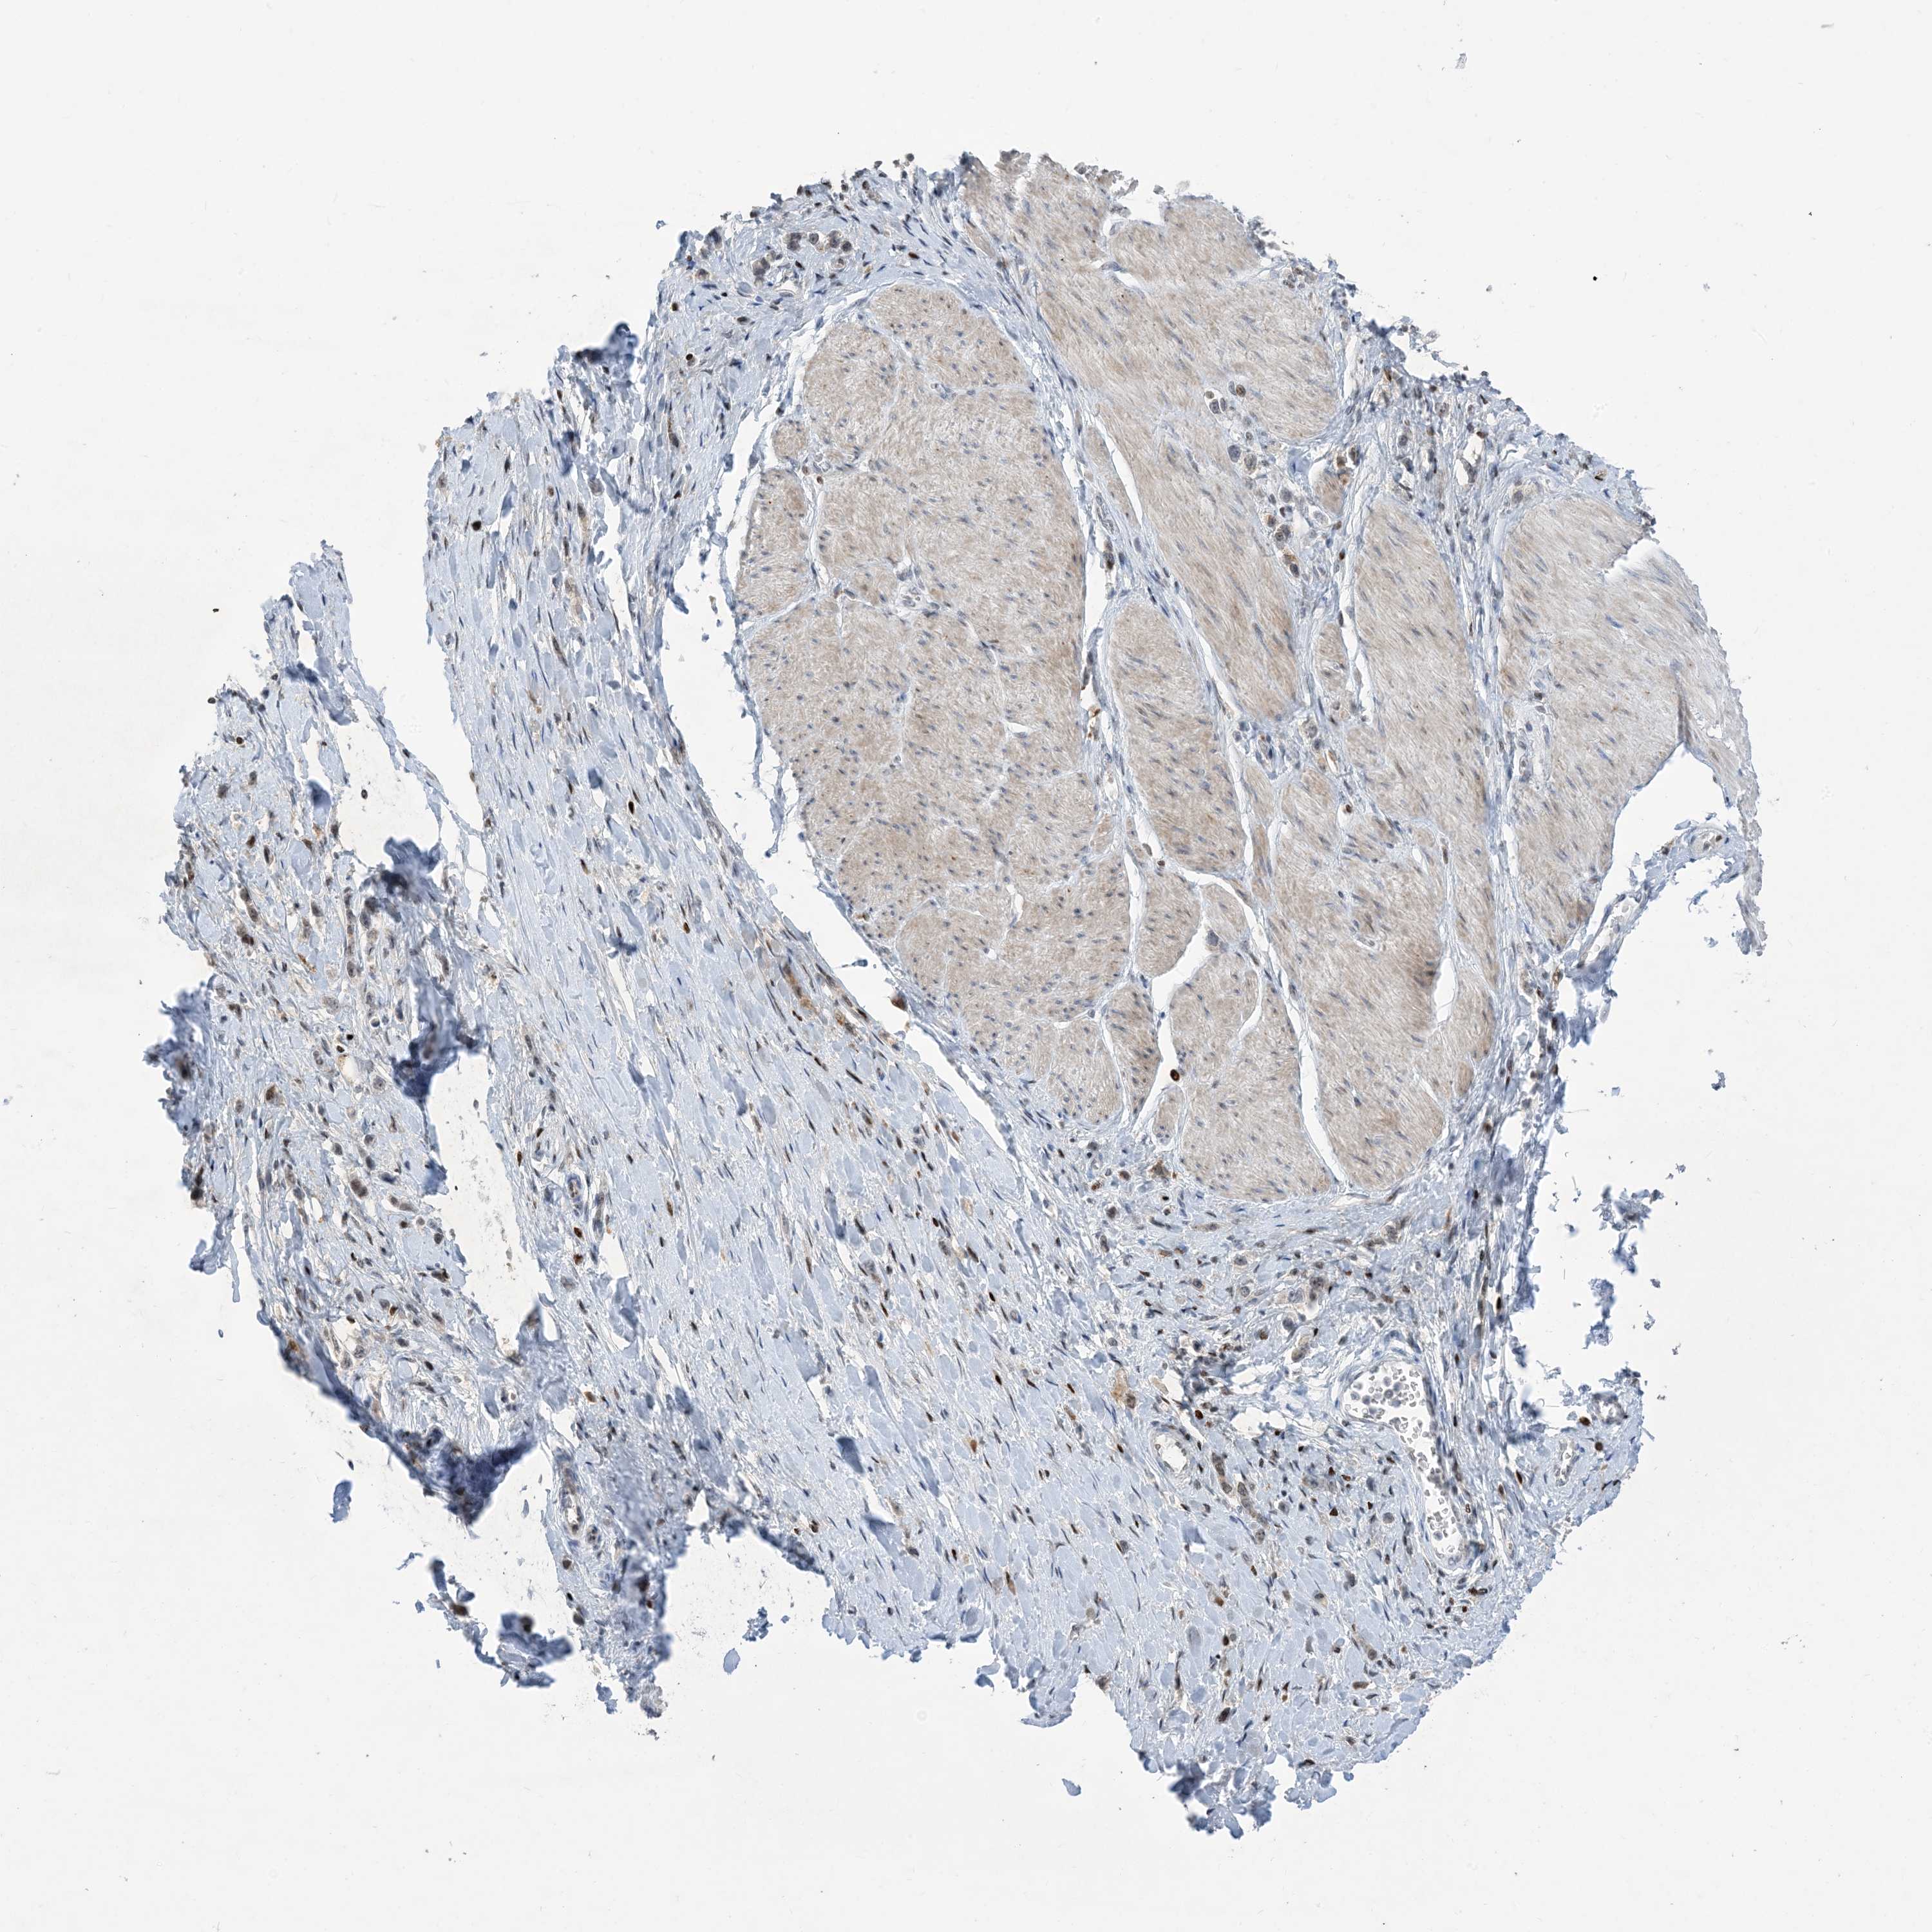

STOMACH CANCER - Protein expressioni

A mouse-over function shows sample information and annotation data. Click on an image to view it in a full screen mode. Samples can be filtered based on level of antibody staining by selecting one or several of the following categories: high, medium, low and not detected. The assay and annotation is described here.

Note that samples used for immunohistochemistry by the Human Protein Atlas do not correspond to samples in the TCGA dataset.

Antibody stainingi

Antibody staining in the annotated cell types in the current human tissue is reported as not detected, low, medium, or high, based on conventional immunohistochemistry profiling in selected tissues. This score is based on the combination of the staining intensity and fraction of stained cells.

Each image is clickable and will lead to virtual microscopy that enables deeper exploration of all samples and also displays staining intensity scores, fraction scores and subcellular localization as well as patient and tissue information for each sample.

Antibody HPA034959

Staining

High

Medium

Low

Not detected

Intensity

Strong

Moderate

Weak

Negative

Quantity

>75%

75%-25%

<25%

None

Location

Nuclear

Cytoplasmic/membranous

Cytoplasmic/membranous,nuclear

Adenocarcinoma, NOS